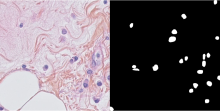

Nuclei segmentation in histopathology images

1602 Example of Histopathology image and matched ground truth histopathology, nuclei

The dataset contains ground truth annotation for the segmentation of the nuclei.

MoNuSeg - Multi-organ nuclei segmentation challenge

1601 MoNuSeg Example histopathology, nuclei

Yes in the form of annotations in html format. MATLAB Code for reading in xml annotations is available in the website.